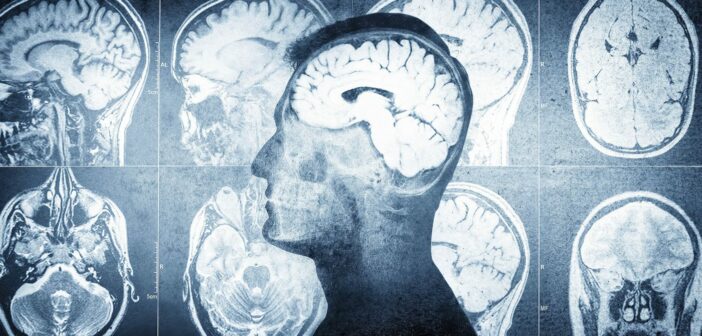

Az emberi agysejtek evolúciója összefüggésben állhat az autizmussal

Egy új tanulmány szerint az emberi agysejtek evolúciója összefüggésben állhat az autizmussal és a neurodiverzitással – írja az Orvostovábbképző Szemle Online.

A tanulmány szerzői úgy gondolják, hogy az emberi agy evolúciójának sebessége segíthet megmagyarázni, miért fordul elő autizmus az emberi fajban.

A szerzők szerint az autizmussal kapcsolatos bizonyos gének az emberben más fajokhoz képest alulreguláltak, és az autizmus az emberi kognitív tulajdonságok gyors evolúciójának mellékterméke lehet. Az emberi agy kétségtelenül igen bonyolult és egyedülállóan hatékony. A komplex nyelv, a mélyreható előre tervezés, a mély empátia és a kultúra csak néhány azok közül a teljesítmények közül, amelyeket ez a hatékony szerv tett lehetővé. Neurológiai képességeink evolúciós előnyöket jelentettek őseink számára. Lehetővé tették az emberi faj elterjedését a világban, és azt, hogy alkalmazkodjon mindenféle földi környezethez.

Molecular Biology and Evolution című folyóiratban megjelent tanulmány  https://academic.oup.com/mbe/article/42/9/msaf189/8245036 szerzői szerint azonban agyunk szédítően bonyolult áramkörei – és azok fejlődésének sebessége – lehet az oka annak is, hogy az autizmus gyakori a fajunkban.